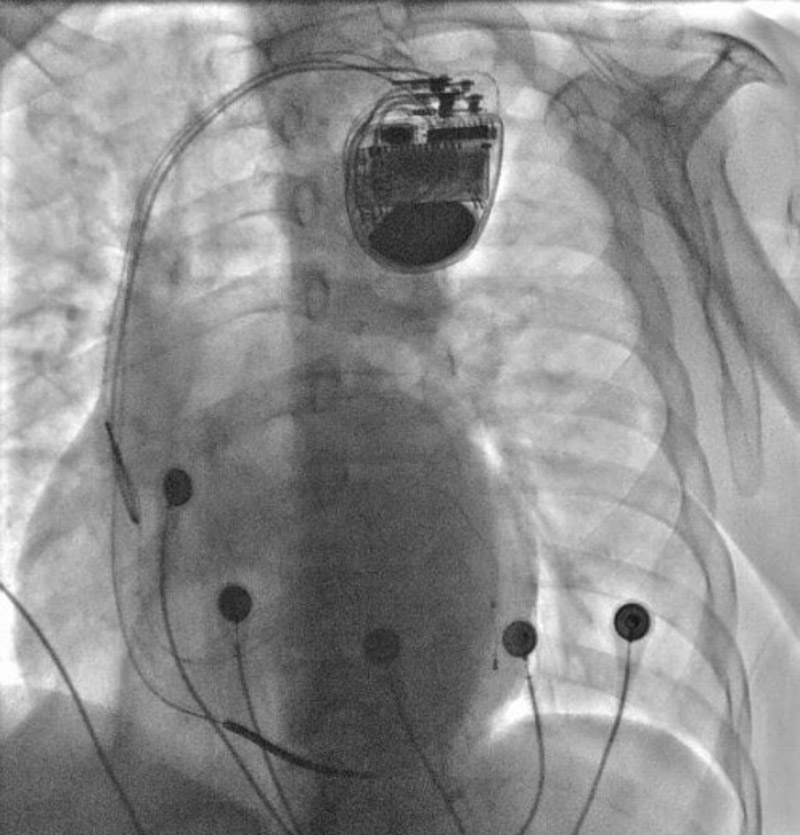

心血管內(nèi)科電生理團隊經(jīng)過術(shù)前詳細的手術(shù)方案討論和制定,術(shù)中精準(zhǔn)操作,成功完成了心臟再同步化除顫起搏器CRT-D植入術(shù)。術(shù)后復(fù)查心電圖示QRS波恢復(fù)到119ms,明顯變窄,患者心臟功能及癥狀較手術(shù)前顯著改善。